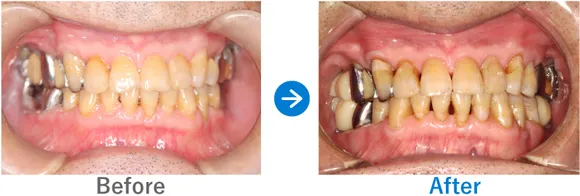

ほぼ虫歯な状態から、できるだけ歯を残した最小限のインプラントできれいな口元に

全顎ランパントカリエス(複数の歯に同時に虫歯が発生する状態)

インプラント4本:上顎2本、下顎2本、残せる歯はすべて補綴治療

4,917,000円(内訳:抜歯テルプラグ、GBR、根管治療、インプラント4本(ストローマン)、ガイド、全顎仮歯、補綴治療、セデーション、保証20年)

※当時の価格で現在とは異なる場合があります。

来院の背景

歯医者が苦手で、子供時代に歯科にかかったきりでした。ほとんどの歯に虫歯がある状態だったため、心配になったお父様が連れてこられました。

治療結果

まだお若いため、残せる歯はできるだけ残したうえで補綴治療(クラウンやブリッジなどによる治療)を行い、どうしても抜歯が必要な歯4本のみインプラントを行う方針で治療を進めました。

治療後は、見た目が整ったことはもちろん、しっかり噛めるようになったと喜んでいらっしゃいました。歯磨きが苦手とのことなので、定期メンテナンスでのアフターフォローも大切です。